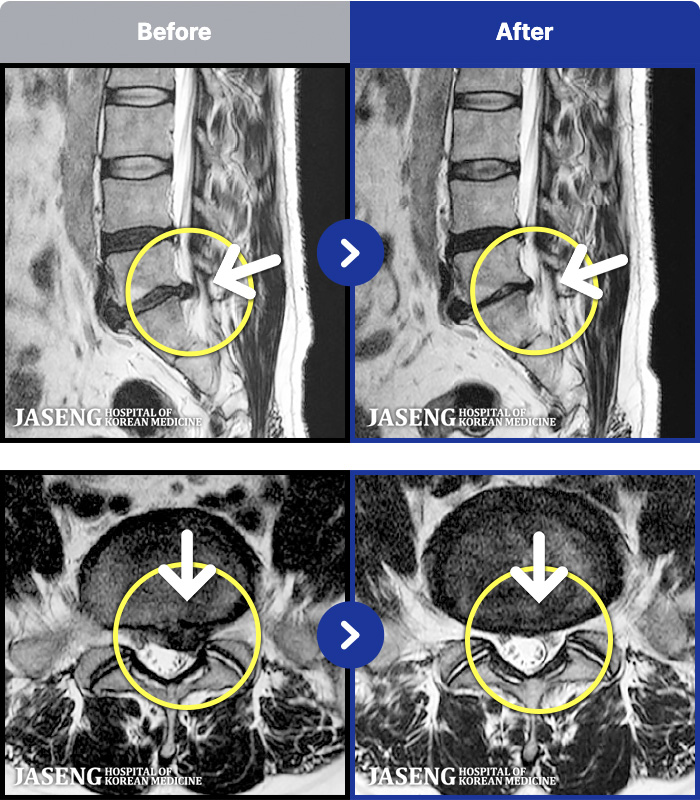

MRI ġ

MRI ũ ʸ Ȯϼ.